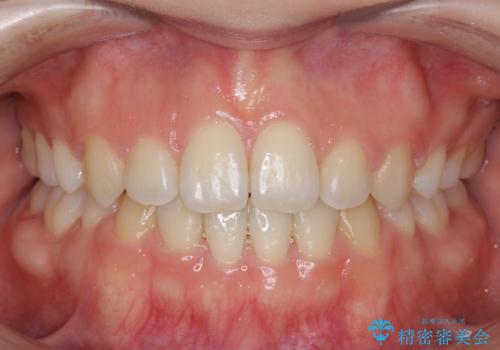

時間はかかりましたがしっかりかみ合わせから治すことができました。

臼歯の反対咬合は簡便なマウスピース矯正で治すのは難しいです。

口元の突出も改善しており理想的な横顔になりました。